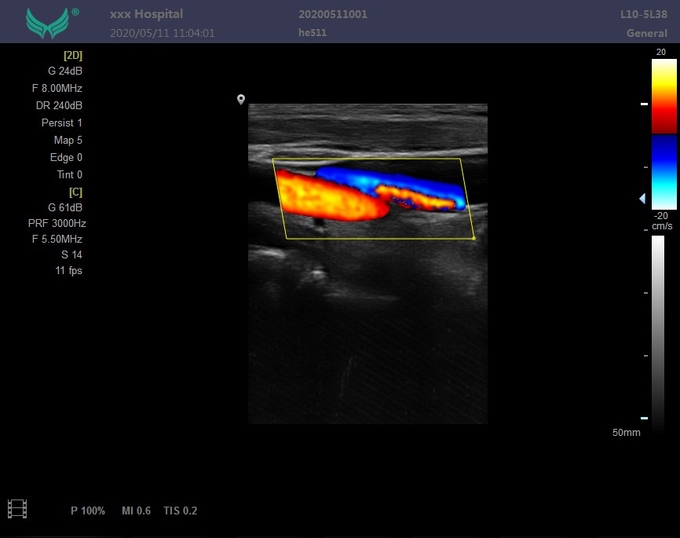

--Режим работы монитора: B, B/B, m, B/M, CFM, CMF/B, PDI, B/PW, CW и другие режимы;